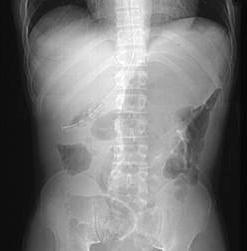

男,23岁,急性左上腹痛,腹胀,结合图像,应考虑为 ( )A、小肠梗阻B、肠套叠C、胃扭转D、结肠梗阻E、结肠扭转

问题 男,23岁,急性左上腹痛,腹胀,结合图像,应考虑为 ( )

选项 A、小肠梗阻 B、肠套叠 C、胃扭转 D、结肠梗阻 E、结肠扭转

答案 E